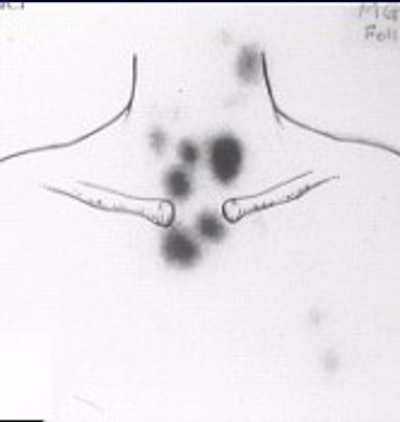

![]() |

| Fifty-three-year-old male with papillary carcinoma who underwent total thyroidectomy. First post-operative scan with 5 mCi 131I at 72 hours. Two foci of remnant metastases are seen. |

| Four weeks later, a scan with 100 mCi 131I at 72 hours was obtained. The stunned lesions failed to take up any of the therapy dose. |

| At one-year follow-up on 5 mCi 131I scan at 72 hours, the same two lesions are present. Images courtesy of Dr. Hee Myung Park. |